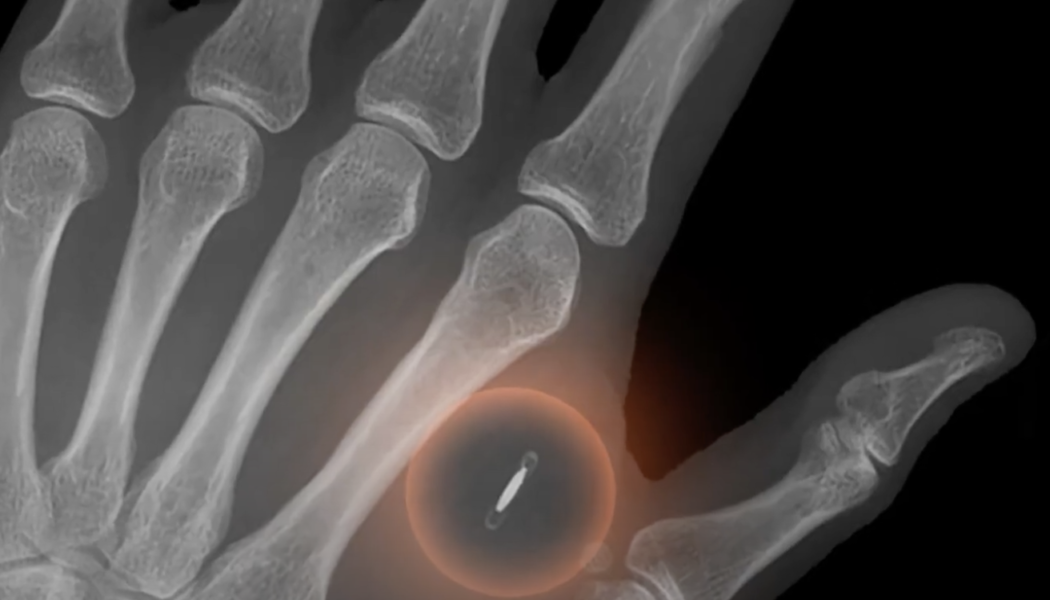

The Lightning Network continues to shock the Bitcoin (BTC) community. A swiss IT Professional called F418 (not his real name) surgically implanted a Lightning-enabled chip into his right hand to make Lightning Network (LN) payments. An X-Ray image of the chip implanted into F418’s hand. Source: Youtube Speaking with Cointelegraph, F418 said he experimented with body modification and LN payments for fun. He does not recommend that Bitcoin enthusiasts take the layer-2 payments network, the LN, into their own hands as he did. “The use is just to show that it is possible and you can do stuff like that.” He added that most people carry cards, it’s just his hand has the wow factor: “It’s funny if you are doing a presentation as I sometimes do presentations about payments and talk to ...